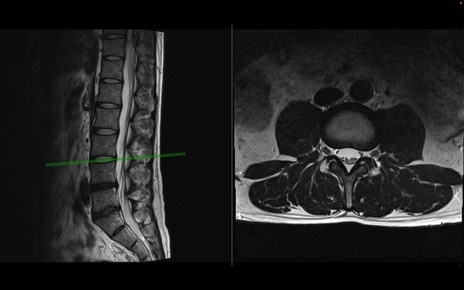

【整形】TIPS症例1 腰椎MRI 横断像と矢状断像

【症例】40歳代男性

【主訴】左臀部〜大腿後面痛み

【現病歴】2週間前から腰痛あり。2日前に夜中にくしゃみをした際に激痛が出現。疼痛強いため来院。

【身体所見】左臀部〜大腿後面、下腿後面のしびれ。SLR -/+ 30度、うつ伏せ困難、筋力低下なし。

異常所見と診断は?